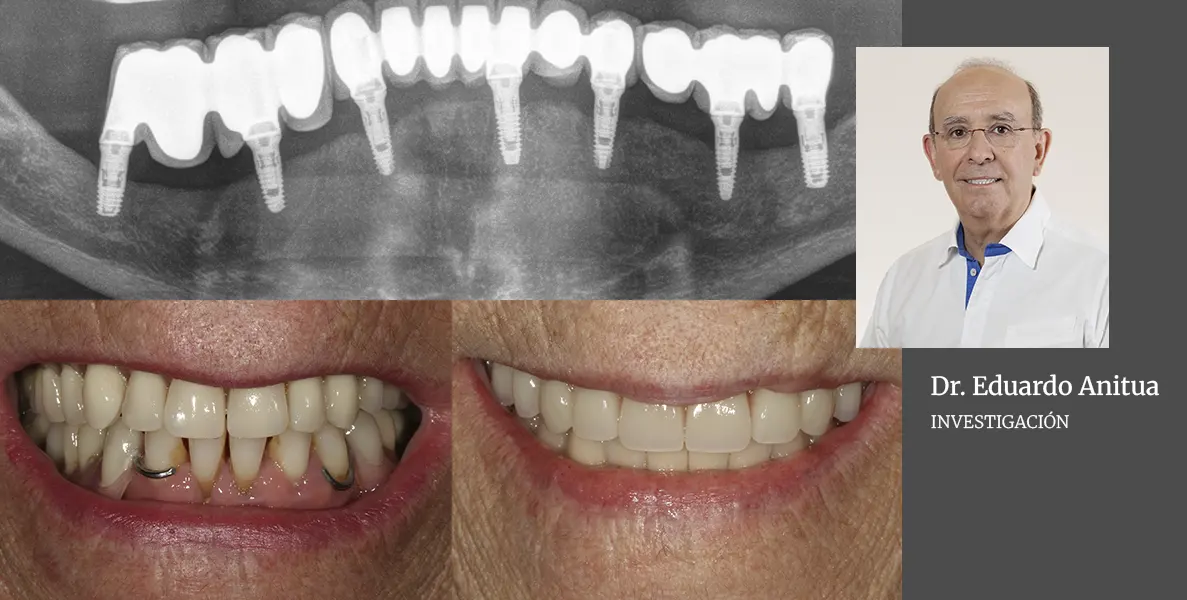

Práctica Odontológica

Tratamiento directo de la atrofia horizontal con implantes extracortos y estrechos (plataforma 3.0 mm) sin técnicas accesorias: un enfoque de mínima intervención